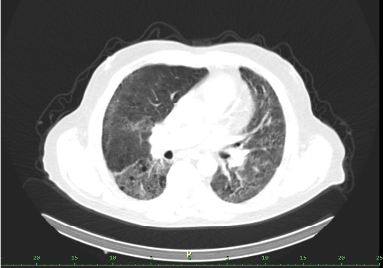

/ Obr. č. 8-10: ldCT plic v rámci vyšetření SPECT/CT. /

SPECT/CT potvrzuje tyto perfuzní defekty. Na ldCT je dále patrná Vámi popisovaná nespecifická intersticiální pneumonie, taktéž emfyzém, to však nevysvětluje diskrepanci mezi perfuzí a ventilací. Jde tedy o tzv. V/P mismatch.